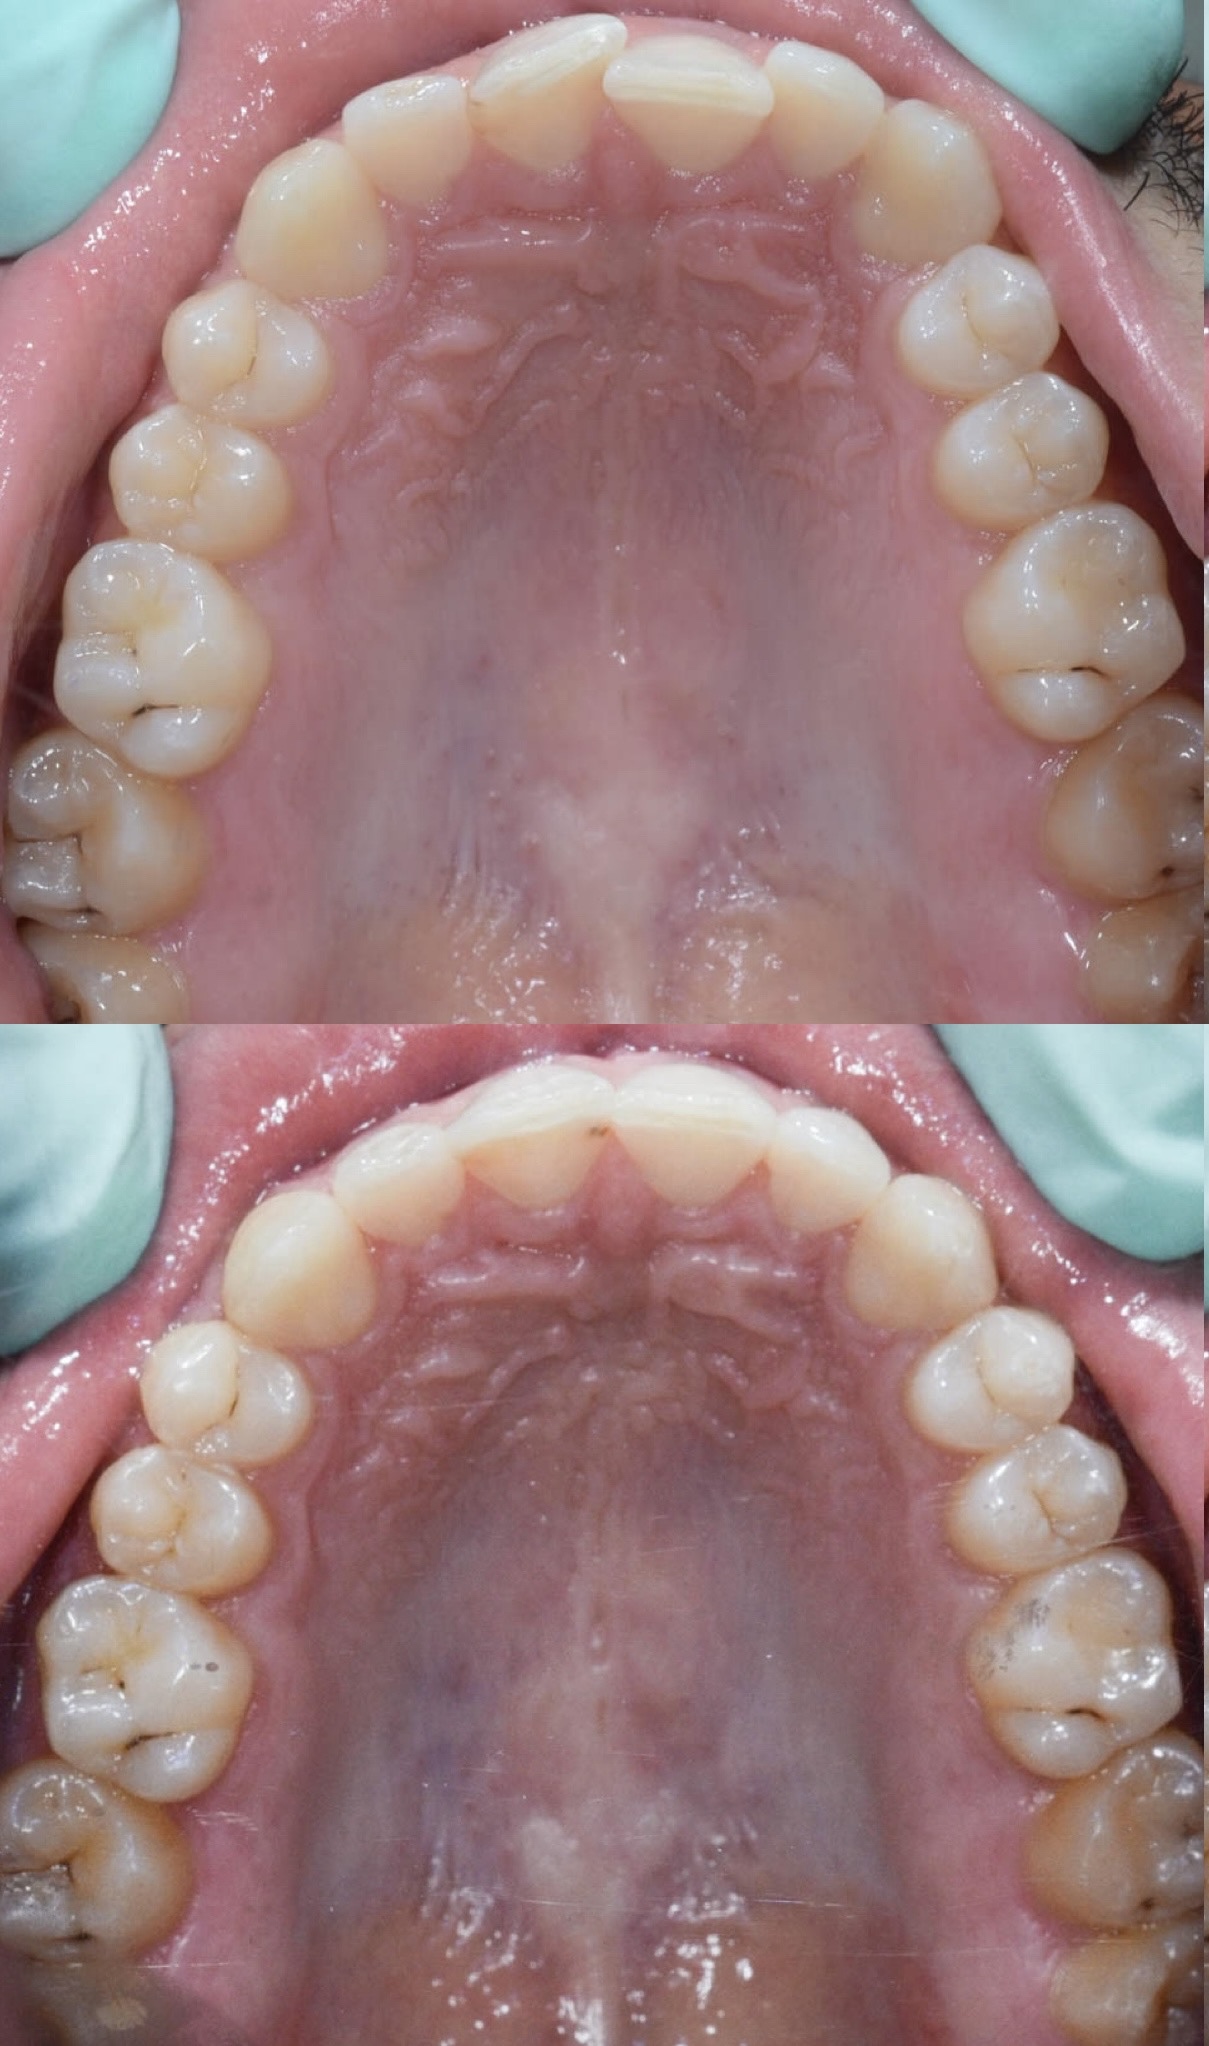

U galeriji slika su prikazani klinički slučajevi ovakvih odraslih pacijenta bilo da se radi samo o ortodontskoj terapiji ili predprotetskoj ortodonciji.

Kompresija –fiksni aparat i ekstrakcija jednog donjeg sjekutića

U sljedećem primjeru prikazan je pacijent s kompresijom koji je već bio u ortodontskoj terapiji. Za rješavanje kompresije donje čeljusti izvađen je sjekutić. Nkon terapije je došlo i do smanjenja recesija na očnjacima jer smo pomakli zubni korijen u bolji položaj.